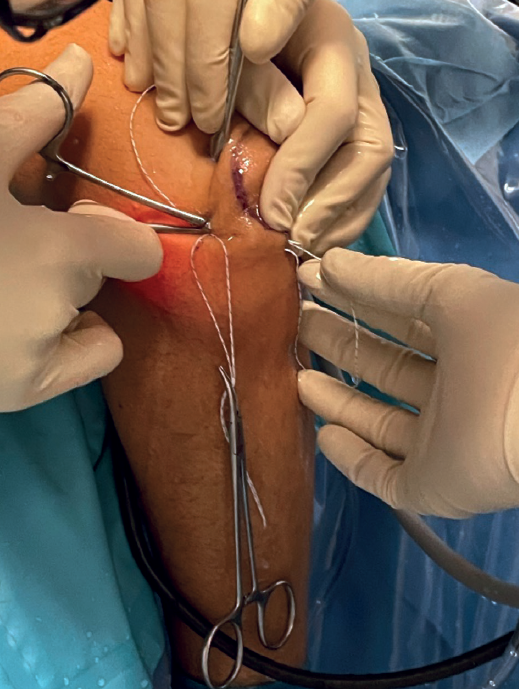

Using a straight mosquito, one end of the suture is retrieved subcutaneously at the soft spot from the origin of the LCL, and the other end is retrieved from the insertion of the LCL (Figure 7).

The subcutaneous pass is then made again with the other piece of suture.

If tension is now applied to both sutures and we observe from the posterolateral portal, the radiocapitellar joint is seen to close following plication (Figure 8).

The arthroscope is removed from the joint, and the two ends are sutured separately, taking care to bury the knots as deep as possible at subcutaneous level.